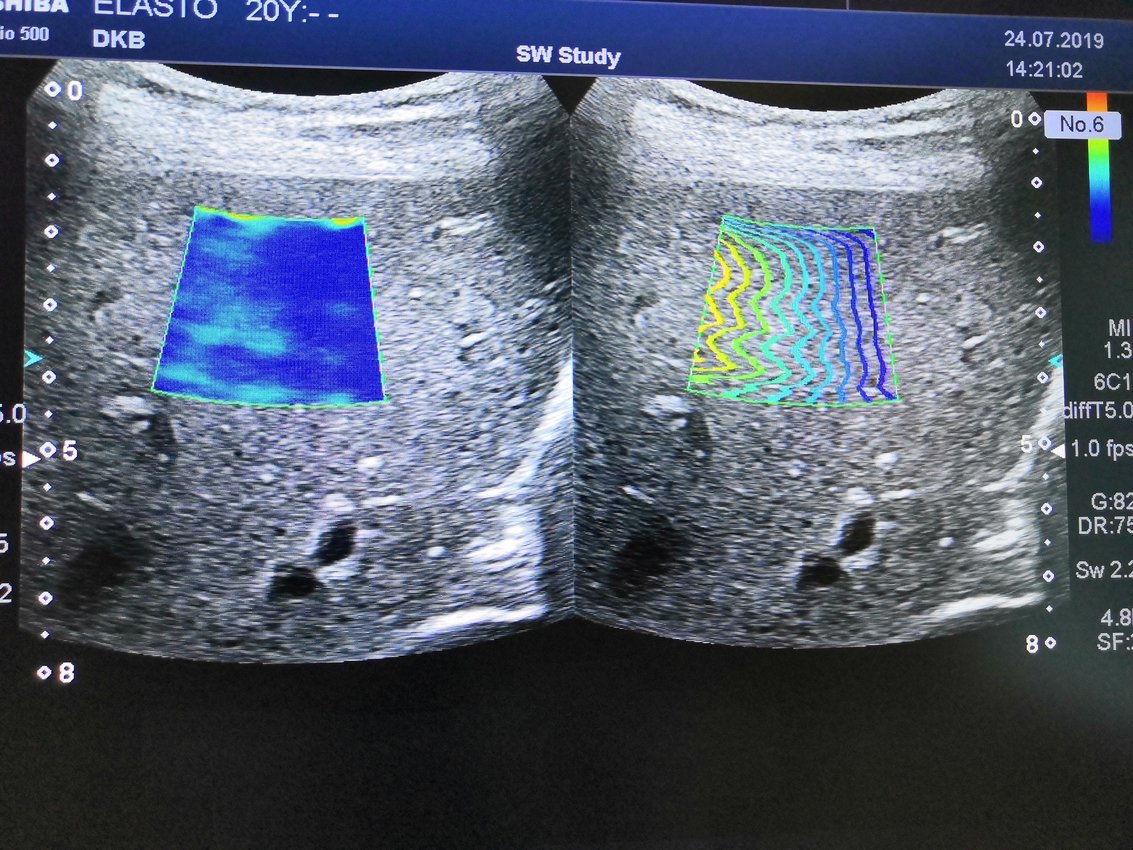

Эластография печени сдвиговой волной. Диагностика фиброза печени.